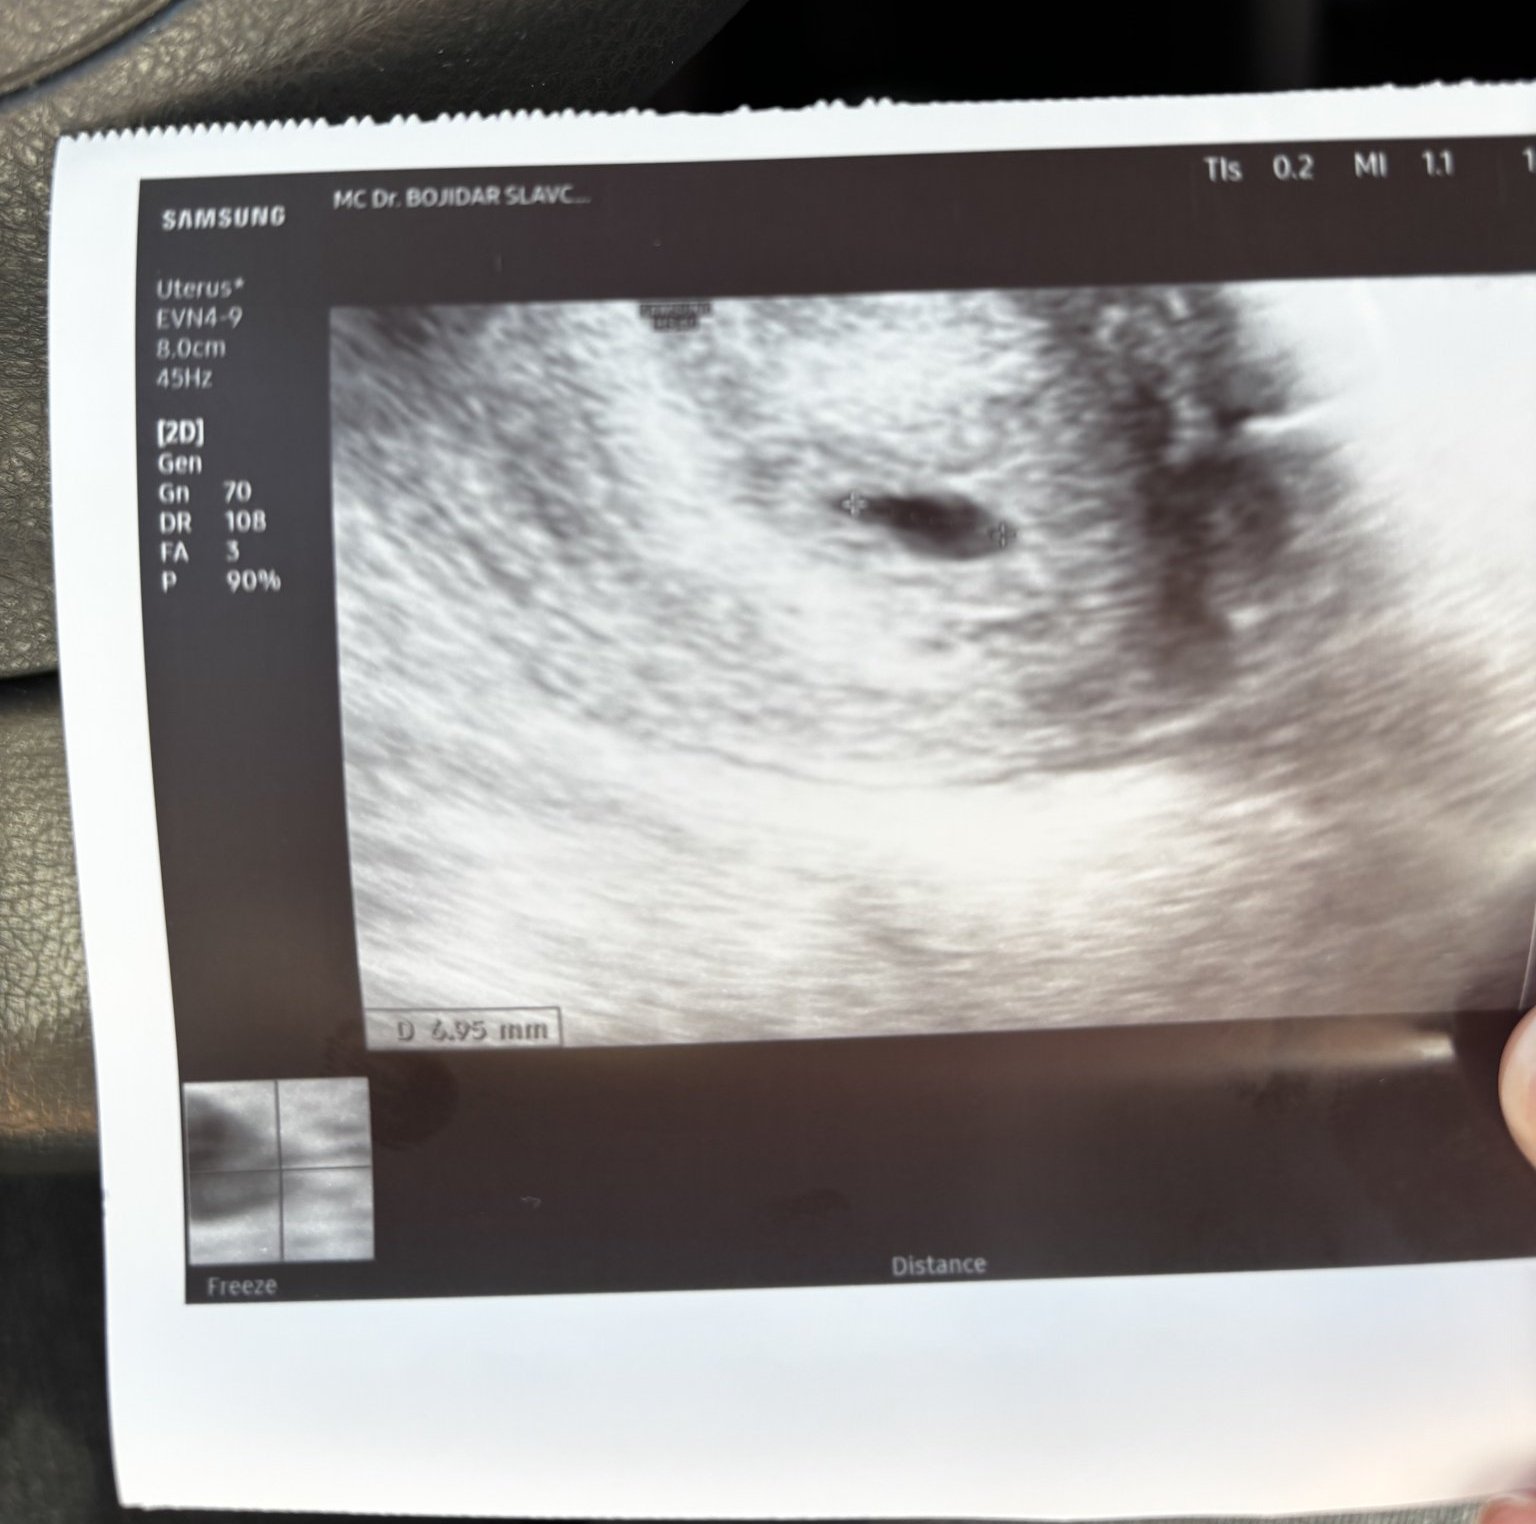

Какво представлява изображението от ехографията на 5-седмична и 2-дневна бременност?

прикачвам тази снимка тук доктора каза че е кухо яйце според вас кухо яйце ли е ?